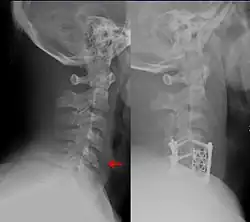

Fracture of the cervical spine (left red arrow showing vertebral body fracture) treated with open reduction and internal fixation (ORIF) (hardware seen on the right)

Patients with spinal cord injury due to trauma tend to have other life-threatening traumatic injuries or complications of spinal cord injury such as neurogenic shock[12] that take precedence to repair of the spine.[6] Thus, spinal motion restriction should be maintained while other medical interventions are begun.[6] Neurological outcomes may be better with early spine repair when possible,[18] however the evidence is low-quality.[12]